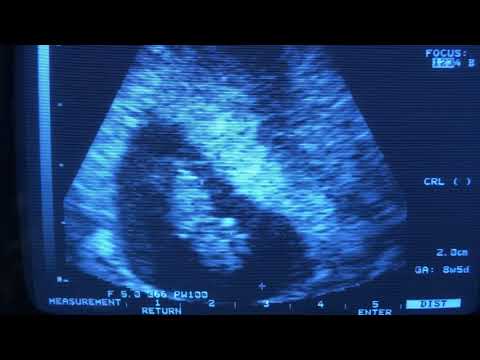

คุณหมออัลตร้าซาวด์ให้ด้วยค่ะ

ดูเป็นรูปเป็นร่างขึ้นมาแล้ว ^_^